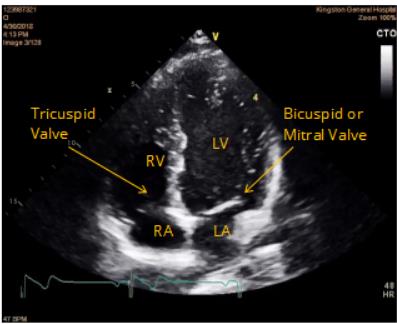

Valves of the Heart

Tricuspid Valve: Between right atrium and right ventricle; has chordae tendinae attached to papillary muscles.

Bicuspid (Mitral) Valve: Between left atrium and left ventricle; also anchored by chordae tendinae.

Clinical Application: Heart Ultrasound

Cardiac ultrasound (echocardiogram) allows visualization of the heart's internal anatomy and valve function. It is used to diagnose heart and valve diseases.